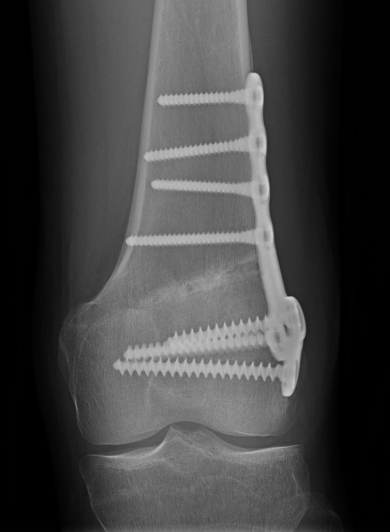

Distal femoral locking plate + bone graft

DFVO 3DFVO 2DFVO 3

DFVO 1DFVO 2

Results

Saithna et al Knee 2014

- 5 year follow up of 18 patients treated with OW DFVO for valgus OA

- 79% survival at 5 years

- 1 nonunion, 2 loss of correction, 1 infection

- 2 persistence of symptoms